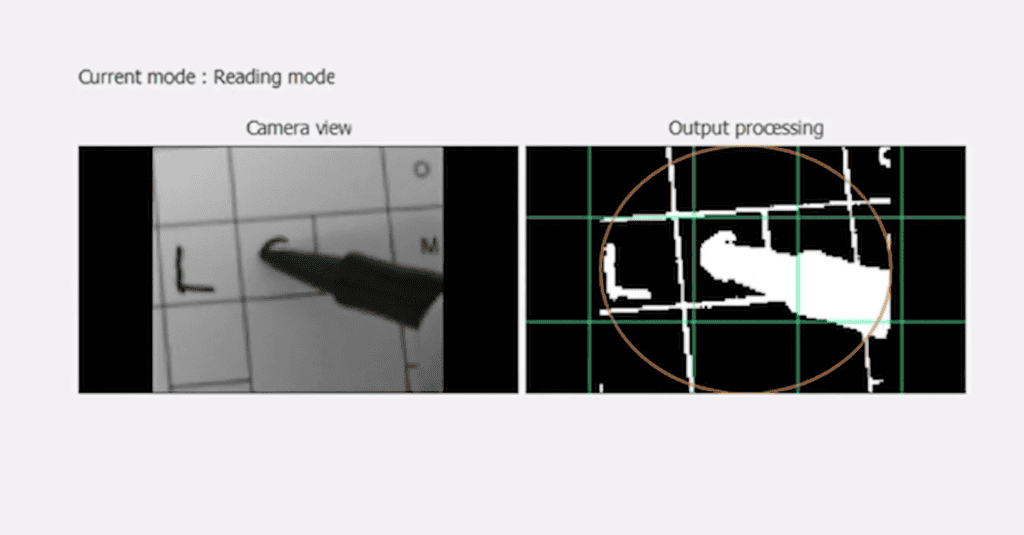

ชิป Prima ประกอบด้วยชิปสี่เหลี่ยมจัตุรัสขนาด 2 มม. ที่ถูกผ่าตัดวางไว้ใต้จอประสาทตา ตรงส่วนหลังสุดของลูกตา โดยใช้เวลาผ่าตัดนานถึง 80 นาที โดยจะใช้งานร่วมกับแว่นตาพร้อมกับกล้องที่จะบันทึกภาพ และส่งแสงอินฟราเรดไปยังชิป แล้วชิปดังกล่าวจะทำหน้าที่เสมือนแผงโซลาร์เซลล์ขนาดเล็ก ที่จะแปลงแสงเป็นการกระตุ้นไฟฟ้า และส่งไปยังสมอง จากนั้นสมองจะตีความสัญญาณดังกล่าวเป็นภาพ ซึ่งเป็นการเลียนแบบกระบวนการการมองเห็นตามธรรมชาติ

Prima แตกต่างจากอุปกรณ์ปลูกถ่ายจอประสาทตาอื่นๆ ตรงที่มันช่วยให้มองเห็นรูปร่าง ลวดลาย และองค์ประกอบภาพอื่นๆ ของวัตถุได้ อย่างไรก็ตาม สิ่งที่ผู้ใช้มองเห็นนั้นไม่ใช่การมองเห็นแบบ “ปกติ” :ซึ่งประการหนึ่งก็คือ ผู้ใช้จะมองไม่เห็นเป็นสี แต่จะมองเห็นเป็นภาพที่ผ่านการประมวลผลแล้วซึ่งจะเป็นสีโทนเหลือง